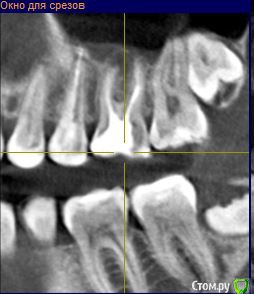

pustoe Опубликовано 13 марта, 2016 Автор Поделиться Опубликовано 13 марта, 2016 Уважаемые врачи, помогите советом! После тройного перелечивания 25 зуба я пол года не обращала внимания на то что чувствую боль при надкусывании. Но надоедает, знаете ли. Ещё раз попыталась понять точно ли 25 болит и выяснила, что боль в 26 зубе. Только при давлении на 1 определённый участок. И боль возникает только при жевании или когда я самостоятельно зубами пытаюсь найти этот участок. На осмотре зуб никак не реагирует ни на давление, ни на воздух, ни на холодную воду. Ну и главное - он мёртвый. Год назад обратилась в клинику, где проводили депульпирование зуба. На снимках врач не нашёл патологий, при ощупывании десны заметил боль в области 28 зуба. Хороший снимок 28 сделать не получилось, направили к хирургу.Посетила хирурга, сделали 3д-томографию. Хирург сказал, что удалять 28 зуб не нужно и проблема в 26, на снимке видна гранулёма. Ниже приложила 2 снимка от хирурга (декабрь 2014 г.). Обратилась в ту же клинику, где лечила 26 зуб , попросила 1) сменить врача, 2) лечить по гарантии. Зуб пролечили (февраль 2015 г.), результаты лечения на снимке №299 (сделан в ноябре 2015 г). Боли при надкусывании появились спустя недели 2-3. Далее в связи с переездом в другой город, не было возможности вновь обратиться к лечащему врачу, поэтому обратилась в новую клинику с целью удалить зуб или наткнуться на профессионалов, которые вылечат меня. В ней посчастливилось услышать аж два мнения разных врачей: терапевт сказал, что все дураки и плохо меня пролечили, надо заново перепломбировать каналы и закладывать лекарства, плюс на 25 зубе обнаружил гранулёму (осмотра физически не произвёл в связи с тем, что на час задержал мой приём и за мной был другой пациент, поэтому времени на меня у врача не было). Второй врач-пародонтолог предложил сделать резекцию. Я согласилась на второй вариант, при посещении пародонтолога описала историю зуба, врач засомневалась в наличии гранулёмы, хотя сказала, что на снимке гранулёма видна. Но раз пришла, решили резать. Разрезали десну, ткани здоровые, куча камня. Провели кютераж, гранулёму не нашли. Насколько я поняла, глубоко рыться в корнях врач не стала в связи с тем, что вариант с гранулёмой отмела. Прошёл месяц, две недели назад начала жевать на этой стороне, боли вернулись. Я в растерянности, вы, врачи с форумов, всегда советуете обратиться очно к специалистам, но я в той ситуации, когда это не помогает. Можно сходить и удалить зуб, но не хочется терять его, да и когда я шла к врачам с этой целью, меня убедили сохранить зуб.Скажите, что мне делать? Что вы видите на снимках ноября (самый актуальный снимок). Как может врач видеть на снимке гранулёму, а при разрезе десны не обнаружить её (в квалификации этого врача сомнений нет)? Как мне избавиться от боли? Может кто-то из вас работает в Санкт-Петербурге и готов взяться за меня?Хочу от вас конкретные советы и комментарий к снимку. Ссылка на комментарий

pustoe Опубликовано 13 марта, 2016 Автор Поделиться Опубликовано 13 марта, 2016 Ниже актуальный снимок в лучшем качестве Ссылка на комментарий